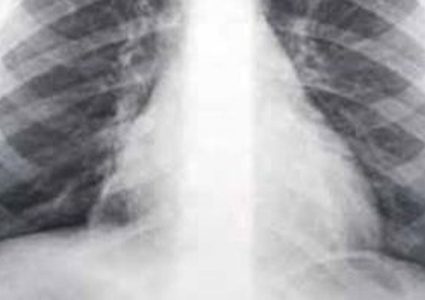

تحدث السيناريست عمرو محمود ياسين، عن تفاصيل الساعات الأخيرة من حياة والده الفنان الراحل محمود ياسين، كاشفا عن معاناته من التهاب رئوي وليس فيروس كورونا …